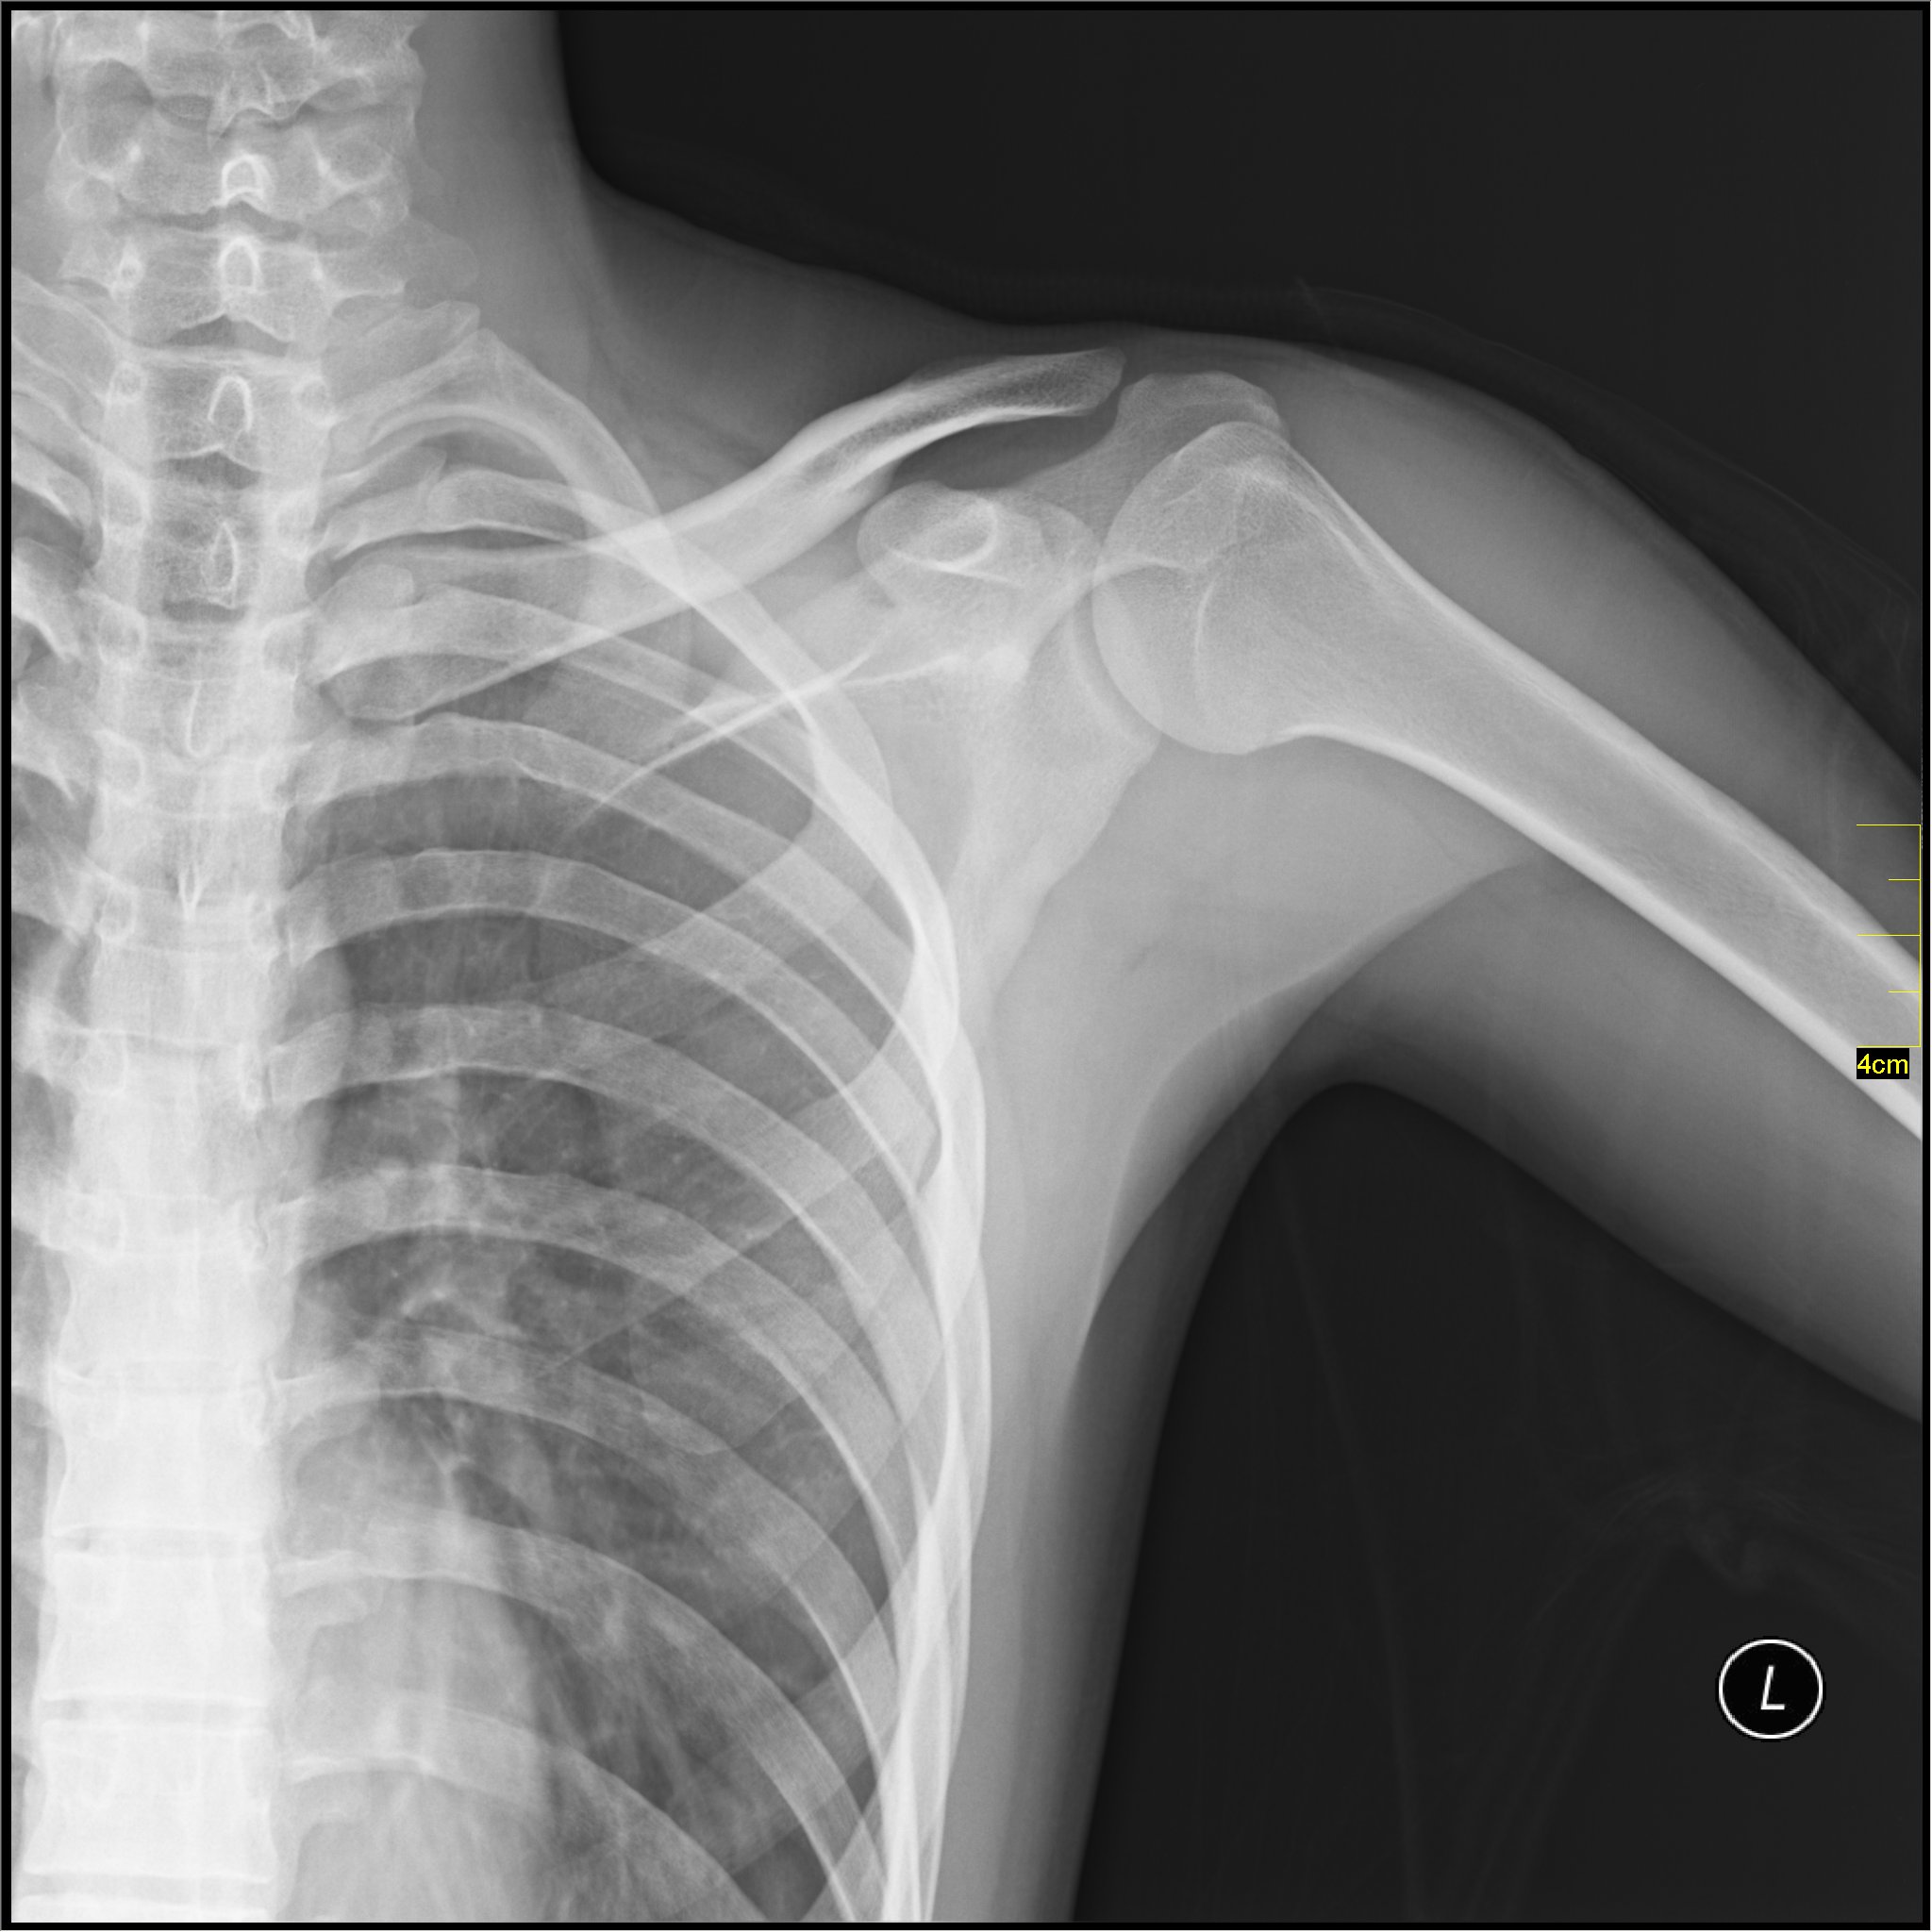

实验1结束后(两手第一指消失)D-81131401手部X光照片

备注:受试者穿越SCP-1314-JP后,指向实验负责人员的手称“你的手怎么多一根手指头”。负责人并未罹患多指症,推测受试者受项目影响记忆或认知产生了异常。此时,观察到受试者有轻度混乱及不安症状。该症状在其他所有实验中也有观测到,只是程度不同。经诊断,受试者的手无论在外观上还是在X光下,除手指缺失之外都显得十分健全。尽管其手部构造会严重影响物体把持,但受试者未报告有障碍。实验2